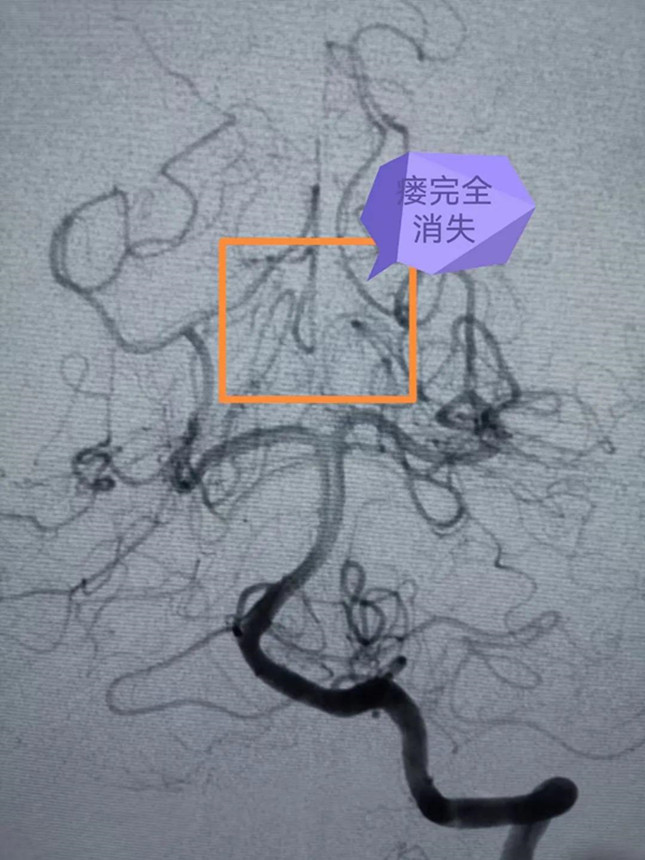

专家团队在大梅的大腿根部股动脉穿入笔芯粗细的导管,然后在脑血管造影机的X线引导下,将一米多长的细若发丝的微导管通过血管小心翼翼送至脑血管畸形部位,由于血管畸形位于脑深部,供血动脉迂曲细长,角度刁钻,手术困难极大,但是专家团队小心仔细,锲而不舍,经过5个多小时的紧张手术,最终将脑血管畸形完全栓塞。手术后,大梅的脑部畸形团块消失,恢复良好。

▲术前DSA影像